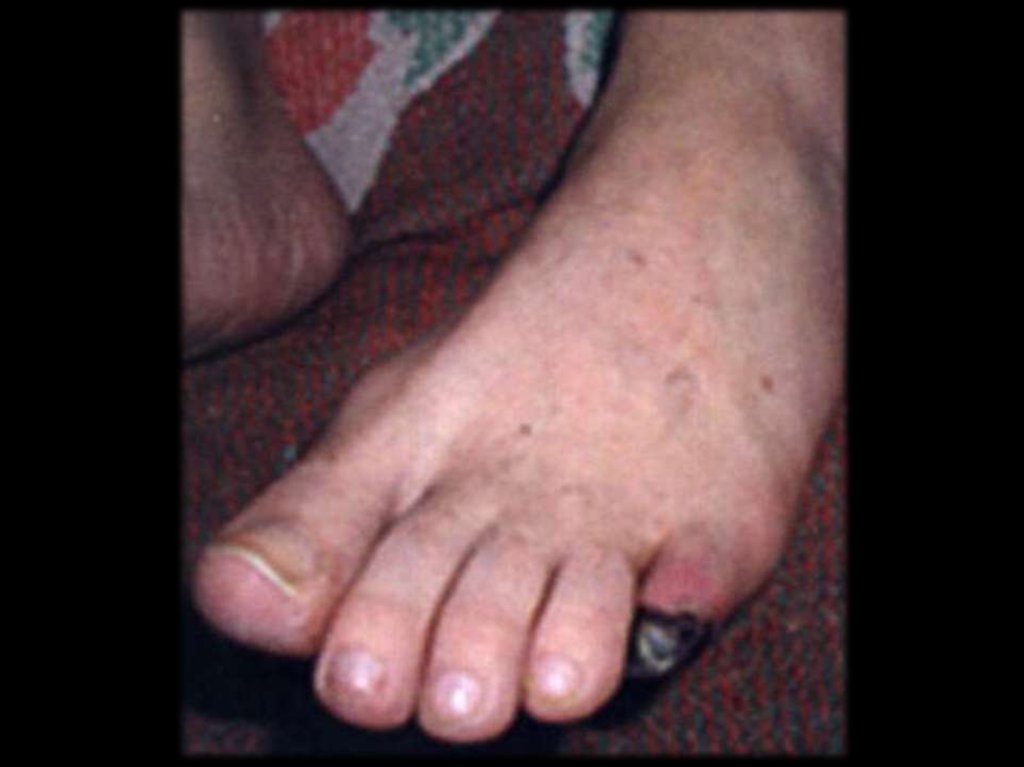

5. кожные изменения, особенно язвы, livedo

reticularis или узелки;

снижение пульсации на тыльной

артерии стопы

3

перемежающая хромота нижних

конечностей

4

трофические язвы

2

венозные тромбозы

биопсия: продуктивнодеструктивный васкулит

сужение или окклюзия дистальных

артерий конечностей

5

Диагноз достоверен при 10 баллов и более при

подтверждении биопсией или

допплерографией. Вероятный – 8 – 9 баллов.